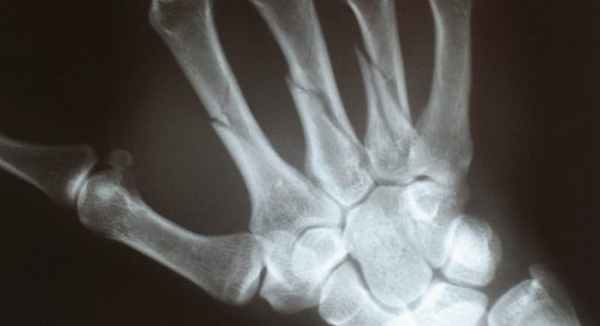

Перелом ладьевидной кости

Перелом ладьевидной кости, как правило, возникает при падении на вытянутую разогнутую кисть, при прямом ударе по ладонной поверхности кисти и др. Особенность кровоснабжения ладьевидной кости обусловливает различные варианты лечения переломов данной кости.

Клиническая картина при переломе ладьевидной кости: в большинстве случаев при осмотре выявляется отечность в области анатомической табакерки, движения в тыльно-лучевом направлении ограничены болью, пациент обычно не может сжать кисть в кулак. Диагностика перелома ладьевидной кости включает рентгенологическое обследование в трёх проекциях (прямой, боковой и косой), в некоторых случаях выполняется РКТ и МРТ.

Чаще всего перелом кисти руки происходит при падении человека или сильном ударе руки. Так как все 27 косточек, составляющих кисть, тонкие, непрочные, а мягких тканей вокруг них мало, то при направленном силовом воздействии они принимают удар на себя. Вследствие этого они трескаются, разламываются. Повреждение каждой кости имеет свою специфику. Например, при переломе ладьевидной кости:

- образуются два осколка;

- происходит внутри- и внесуставное повреждение;

- может возникать вывих полулунной кости.